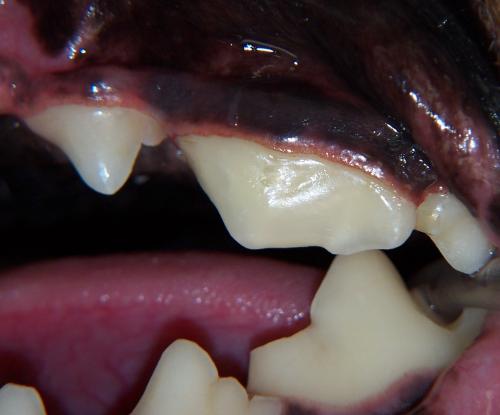

Complicated crown fracture with pulp exposure